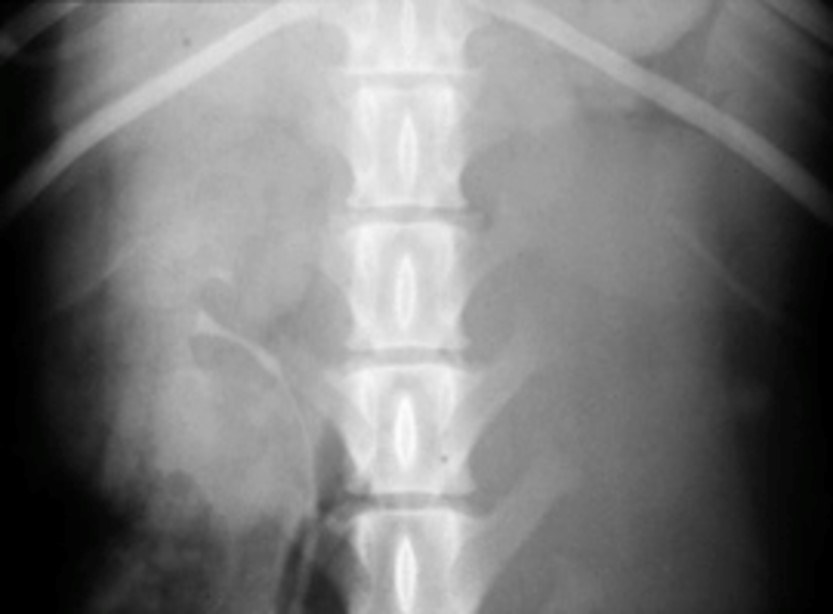

What does this show?

Left – large soft tissue structure. Non contrast; non filtering enlarged L kidney

R – some contrast in ureter and leaving renal pelvis